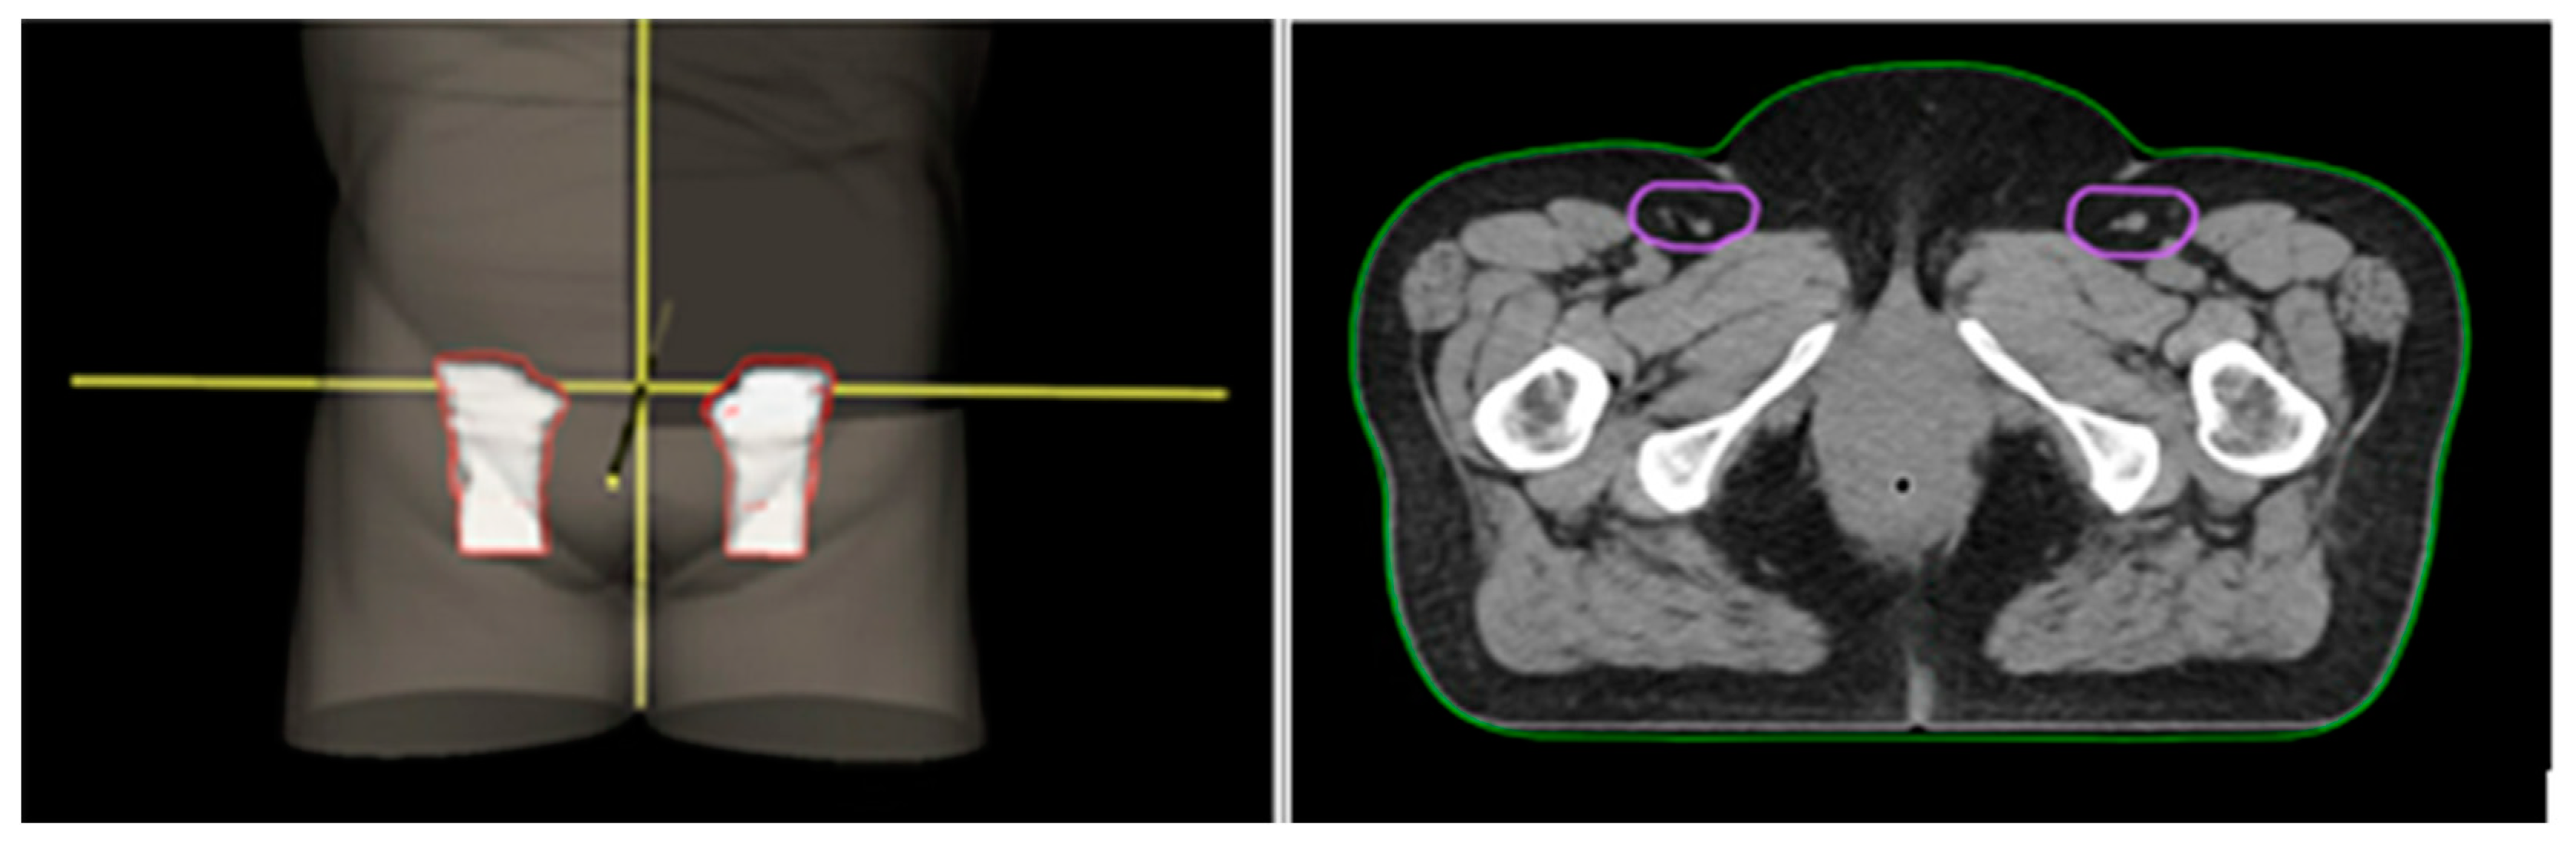

3.2.1. Inguinal Nodes

3.2.2. Ano-Inguinal Lymphatic Vessels

- The ano-inguinal lymphatic drainage (AILD) that is located in the subcutaneous adipose tissue of the proximal medial thigh can be considered as a risk volume. We do not recommend the routine inclusion of the ‘true’ AILD in the contouring volume for pSCCs, but we highlight the fact that the management of this anatomical region remains an issue to be investigated and considered on a case-by-case basis.

- We suggest including the inguinal nodes within the elective volumes. Nevertheless, the omission of inguinal irradiation for SCCs of anal canal cancers < 1 cm could be an option.